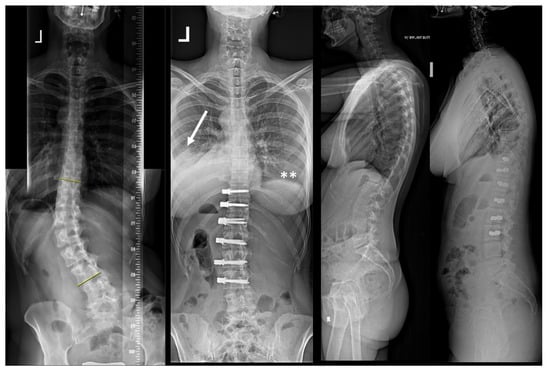

| Patient | Age (Years) | Sex | Curve Type | Instrumented Levels | Complication | Time to Diagnosis | Side of the Complication | Symptoms | Treatment |

|---|---|---|---|---|---|---|---|---|---|

| 1 | 13.3 | F | 2 | T5-T12 right T12-L4 left | Pleural effusion | 2 weeks | Right | Minor dyspnea | Ultrasound, conservative treatment |

| 2 | 17.6 | F | 4 | T6-L1 right | Pleural effusion | 2 weeks | Right | Dyspnea, fatigue | 2 × aspiration |

| 3 | 16.2 | F | 4 | T5-T12 right | Contralateral atelectasis | 2 days | Left | Severe dyspnea | Re-intubation for 3 days, 3 bronchoscopies and removal of a mucus plug |

| 4 | 17.6 | M | 1 | T9-L3 right | Pleural effusion | 4 weeks | Right | Chest pressure | Chest tube reinsertion |

| 5 | 16.2 | F | 2 | T5-T11 right T11-L3 left | Pleural effusion | 3 weeks | Bilateral | Chest pain and elevated CRP levels | Bilateral aspiration, forced diuresis and i.v. albumin treatment |

| 6 | 17.7 | F | 2 | T5-T11 right T11-L3 left | Chylothorax | 3 days | Right | None effusion, diagnosed on routine post-op X-ray | Chest tube reinsertion and dietary restriction |

| 7 | 16.8 | M | 2 | T5-T11 right T11-L4 left | Pleural effusion | 3 weeks | Left | Unknown | Explorative thoracoscopy |

| 8 | 17.9 | F | 1 | T10-L3 left | Pleural effusion | 4 days | Left | None, effusion diagnosed on routine post-op X-ray | Aspiration followed by chest tube reinsertion for recurrent effusion |

| 9 | 14.6 | F | 2 | T5-T11 right T11-L4 left | Pleural effusion | 3 weeks | Right | Fatigue, dyspnea | Chest tube reinsertion, antibiotics for co-existing pyelonephritis |

| 10 | 14.3 | F | 1 | T11-L4 left | Pleural effusion with concomitant infection | 3 weeks | Left | Sudden sharp pain in the left chest and dyspnea | Attempted aspiration and chest tube without output. VATS and six weeks antibiotitcs because of postivie culture for staph epidermidis |

| 11 | 12 | F | 4 | T5-T11 right | Haematothorax | 1 day | Right | No symptoms, significant blood loss noticed after declamping the chest tube and drop of haemoglobin levels | Emergency explorative thoracotomy using the same surgical approach. No active bleeding found but clotted hematoma |

| 12 | 13 | F | 2 | T6-T12 right T12-L4 left | Haematothorax | 6 weeks | Right | Acute chest pain | Emergency explorative thoracotomy |

| 13 | 16.5 | M | 1 | T10-L4 left | Pleural empyema | 5 weeks | Left | Dyspnea, elevated CRP levels | VATS and antibiotic therapy |

| 14 | 16.3 | F | 2 | T5-T11 right T11-L4 left | Pleural effusion | 5 weeks | Right | Dyspnea | Aspiration |